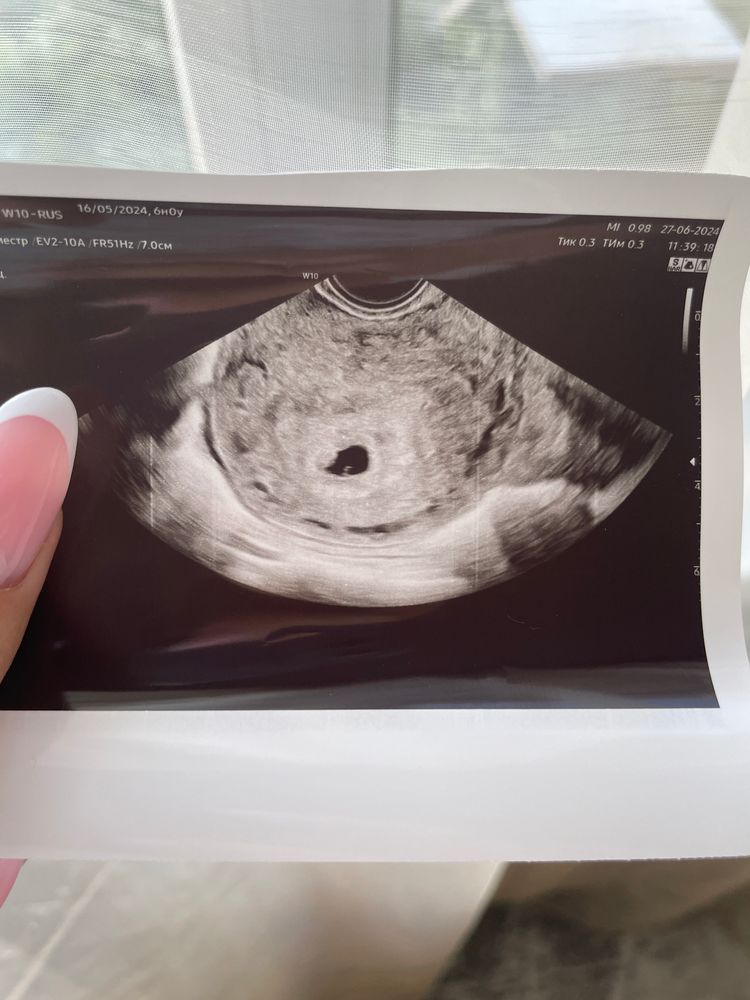

Беременность 6 недель эмбрион не визуализируется

Страхи, переживания и немножечко нытьяЗдравствуйте,у меня беременность По акушерским срокам 6 недель Плодное яйцо диаметр 11 мм правильной формы Эмбрион четко не определяется Желточный мешок диаметром 2,4 мм Хорион кольцевидный толщина 3 мм кровоток по контуру определяется Желтое тело в левом яичнике с активным переферическим кровотоком размер 16 мм Врач написала узи в динамике через 10 дней. Хожу переживаю. В декабре прошлого года была замершая . Сейчас врач назначила дюфастон 2 раза в день. Нормально ли что еще эмбрион не определяется и не слышно сердцебиение?

на фото прям совсем горошинка маленькая